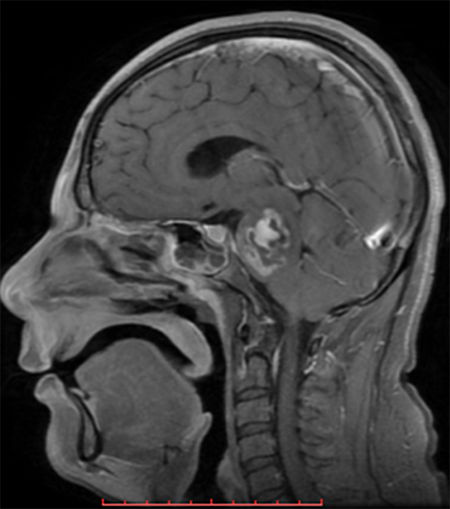

Figura 1. Resonancia magnética cerebral encorte sagital y secuencia T1 con gadolinio.

h.1) Resonancia magnética cerebral con corte sagital y secuencia T1 con gadolinio. Se encontró imagen heterogénea, con efecto de masa y zonas de reforzamiento en el interior. (Figura 1).

Figura 1. Resonancia magnética cerebral encorte sagital y secuencia T1 con gadolinio.